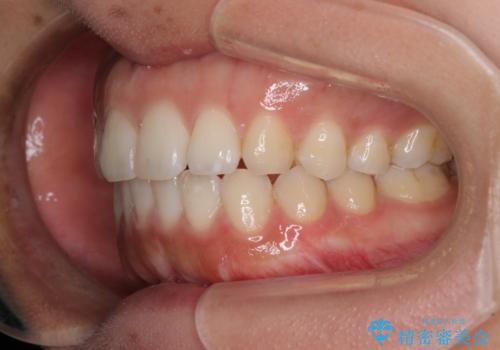

- 上下の前歯のでこぼこを気にして来院された患者様です。

結婚式が近いこともあり、全く目立たない裏側矯正により口元を整えることとしました。

下顎が左側にずれているため、裏側矯正ということもあり咬み合わせを整えるのに時間がかかってしまいました。